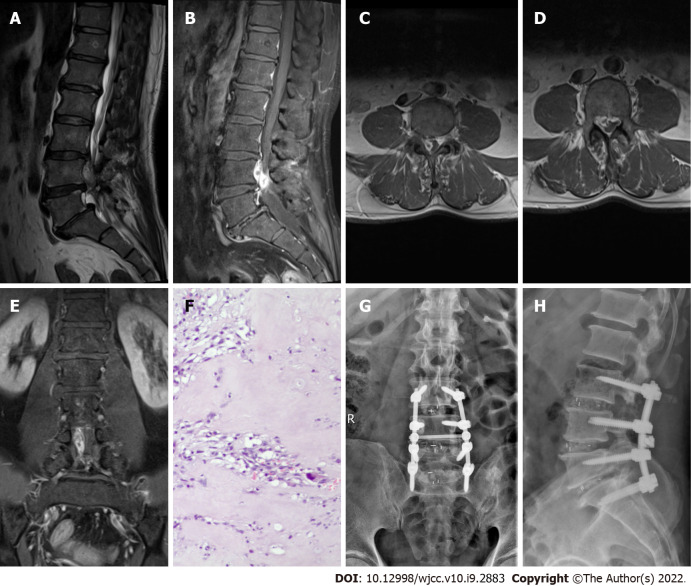

Case 4: After admission, an abnormal shadow was observed in the right intervertebral foramen of the L3 vertebral canal on MRI, and the adjacent dural sac was compressed. The T1-weighted image showed moderate signal intensity, while the T2-weighted image showed high signal intensity. There was no obvious enhancement on contrast-enhanced MRI (Figure 4A-4E).

Imaging examination of case 4. A: Preoperative T1-weighted MRI image showing moderate signal intensity; B and C: Preoperative T2-weighted image showing high signal intensity, and an axial T2-weighted image demonstrating disc fragments in the right anterior epidural space; D and E: Preoperative contrast-enhanced MRI suggested no obvious enhancement; F: Postoperative pathology suggested intervertebral disc tissue; G and H: X-ray on postoperative day 2 indicated intact internal fixation.

Case 4: A hemilaminectomy, discectomy, and internal fixation were performed (Figure 4G–4H). The focus was located in the right anterior epidural space, compressing the dural sac and right L3 nerve root. Postoperative pathology confirmed that the focus was intervertebral disc tissue (Figure 4F).

Case 1 showed high signal intensity on the T1-weighted image, low signal intensity on the T2-weighted image, and heterogeneous enhancement on contrast-enhanced MRI (Figure 1A–1E). Case 2 had low signal intensity on the T1-weighted image, low signal intensity on the T2-weighted image, and heterogeneous peripheral enhancement on contrast-enhanced MRI (Figure 2A–2E). These two cases were diagnosed as neurilemmomas before the operation. Case 3 displayed high signal intensity on the T2-weighted image and obvious peripheral enhancement on contrast-enhanced MRI (Figure 3A–3E). Case 4 exhibited moderate signal intensity on the T1-weighted image and high signal intensity on the T2-weighted image, without enhancement on contrast-enhanced MRI (Figure 4A–4E). These two cases were initially diagnosed as spinal tumors before the operation. Due to the nonspecific imaging findings, we were unable to diagnose these four patients by computed tomography, MRI, or enhanced MRI, so surgery was performed. The focus and adjacent intervertebral disc were resected, the intervertebral space was bone-grafted, and internal fixation was performed. The resected lesions were sent for pathological diagnosis. All four cases were pathologically diagnosed as herniated disc tissue (Figure 1F–4F).